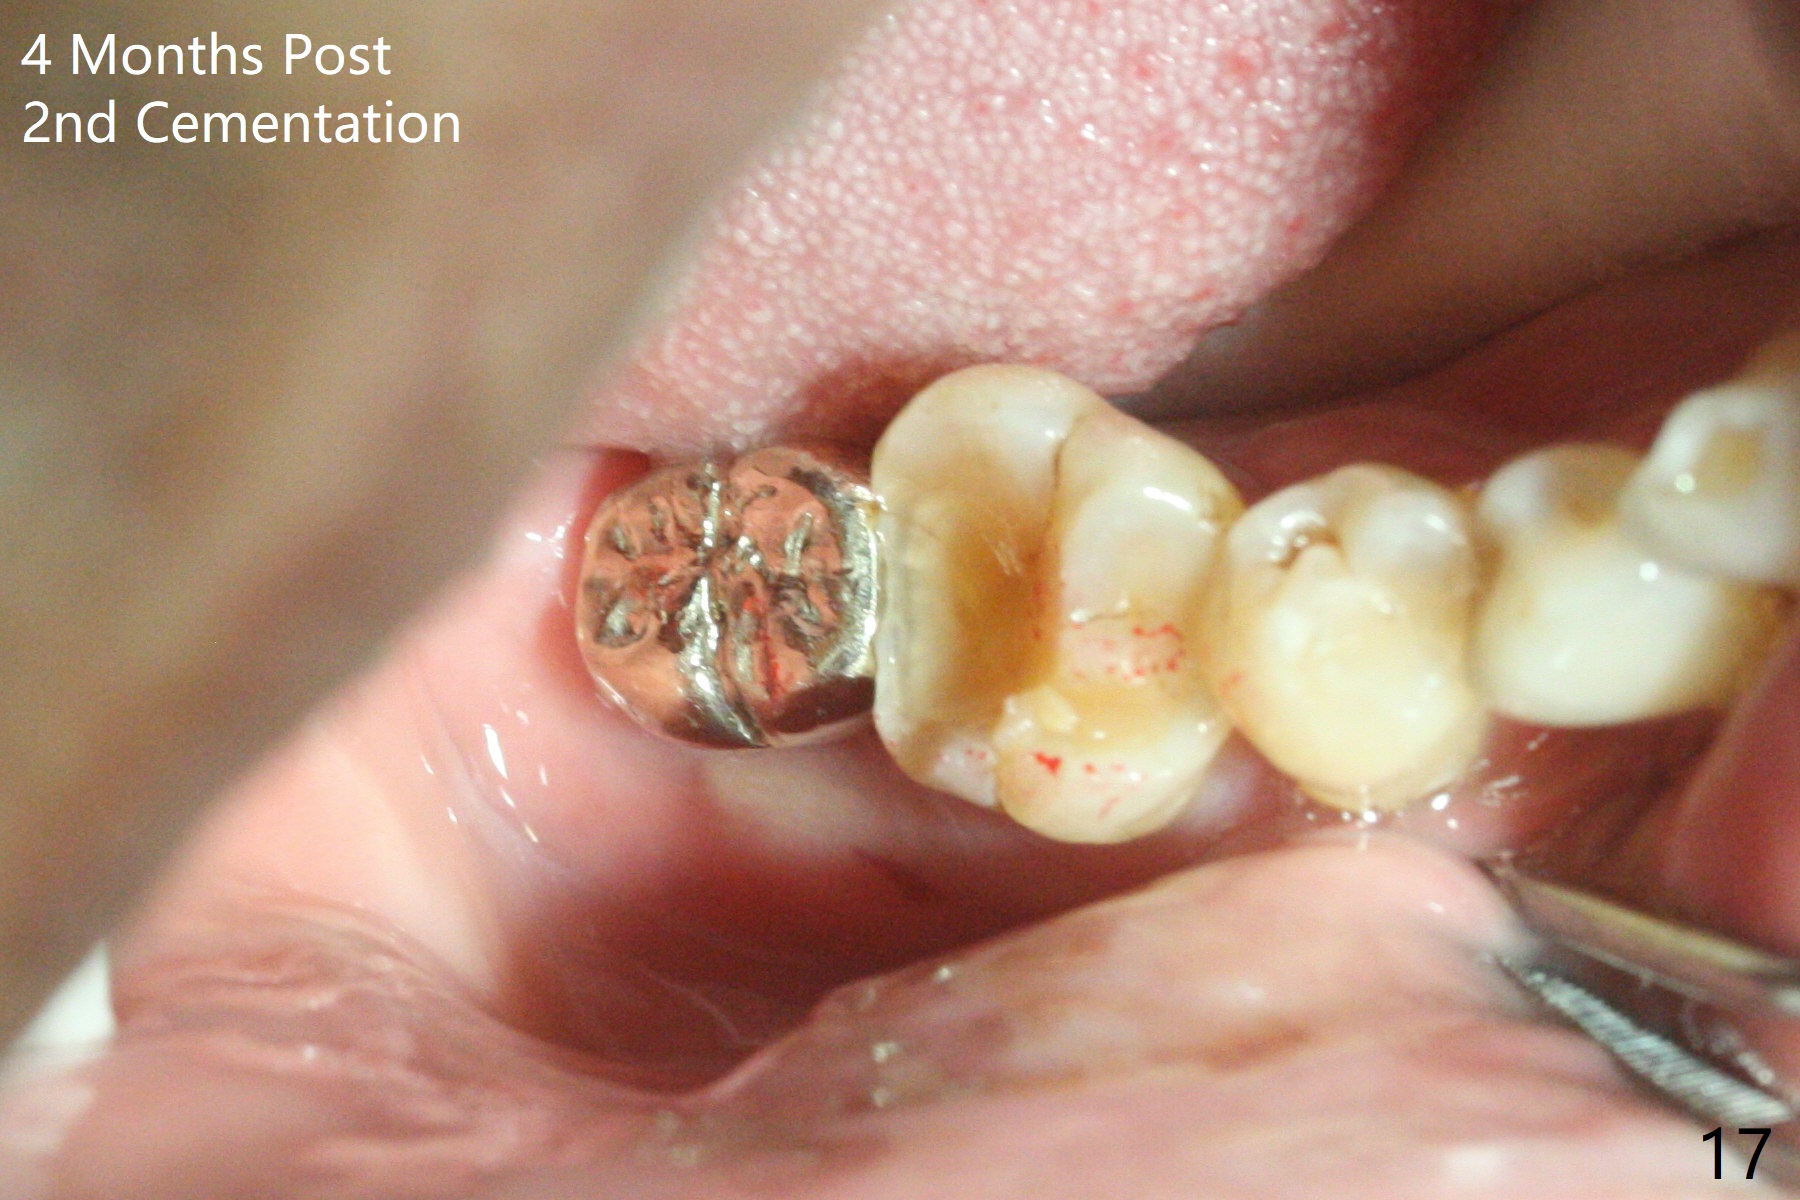

The residual roots of the tooth #31 are lower buccal (Fig.1 B), which in fact is molded and worn by the supraerupted tooth #2. When the tooth is extracted (Fig.2) and an implant, abutment (Fig.3 gold colored) and allograft (*) are placed, the abutment has to be trimmed. An atypical immediate provisional is fabricated by spreading setting acrylic over the abutment and bone graft (Fig.4 P) with occlusal equilibrium. Advantages of the guided surgery are good position (Fig.3 buccolingual), trajectory and depth (Fig.5,6) of the implant. The buccodistally exposed implant threads are packed with allograft in sufficient amount (Fig.3,5,6 *). The atypical immediate provisional breaks down and dislodges 3 weeks postop (Fig.7). In fact the implant plateau is exposed buccally. A monojet is given to the patient for self cleansing. He is instructed to return in 3 weeks. The exposed implant threads are covered 1.5 months postop (Fig.8). Incomplete abutment seating (Fig.9 <) was not noted until 1 year 3 month post cementation when the crown was mobile (Fig.10). A 6x3 mm healing abutment is placed. Three days later, the crown is sectioned and separated from the abutment. The latter returns to place; due to angulation associated with PA, the gap between the implant and abutment is indistinct (Fig.11). Bitewing is taken; the gap exists (Fig.12 <). The abutment seems to be seated deep; there is apparently soft tissue interference. A 5.2x4(2) mm abutment remains incompletely seated (Fig.13 >). A 5.2x4(3) mm one is completely seated (Fig.14 <). Zirconium crown with an access hole is cemented in the mouth. The crown and abutment is then removed for residual cement removal and reseated and torqued (Fig.15). Four months later, the Zirconium crown is fractured (Fig.16). Impression is retaken for high noble metal crown without access hole for strength (Fig.17).